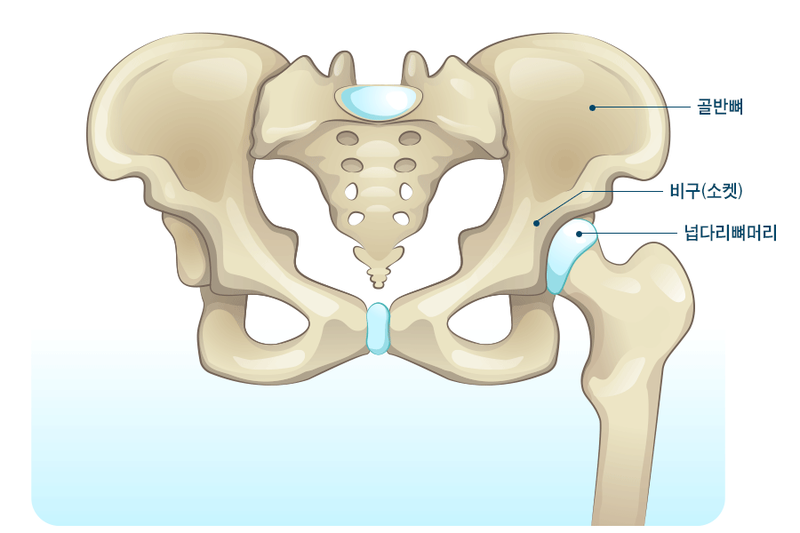

겨울철이 되면 더 위험해지는 노인들의 건강을 위협하는 고관절 골절은 엉덩이관절 주위의 골절을 뜻합니다. 주로 골다골증이 심한 70세 이상의 고령층에서 발생하게 되며 골절이 일어나는 가장 큰 원인으로는 낙상입니다. 그렇기에 겨울철에 특히 조심하셔야 합니다.